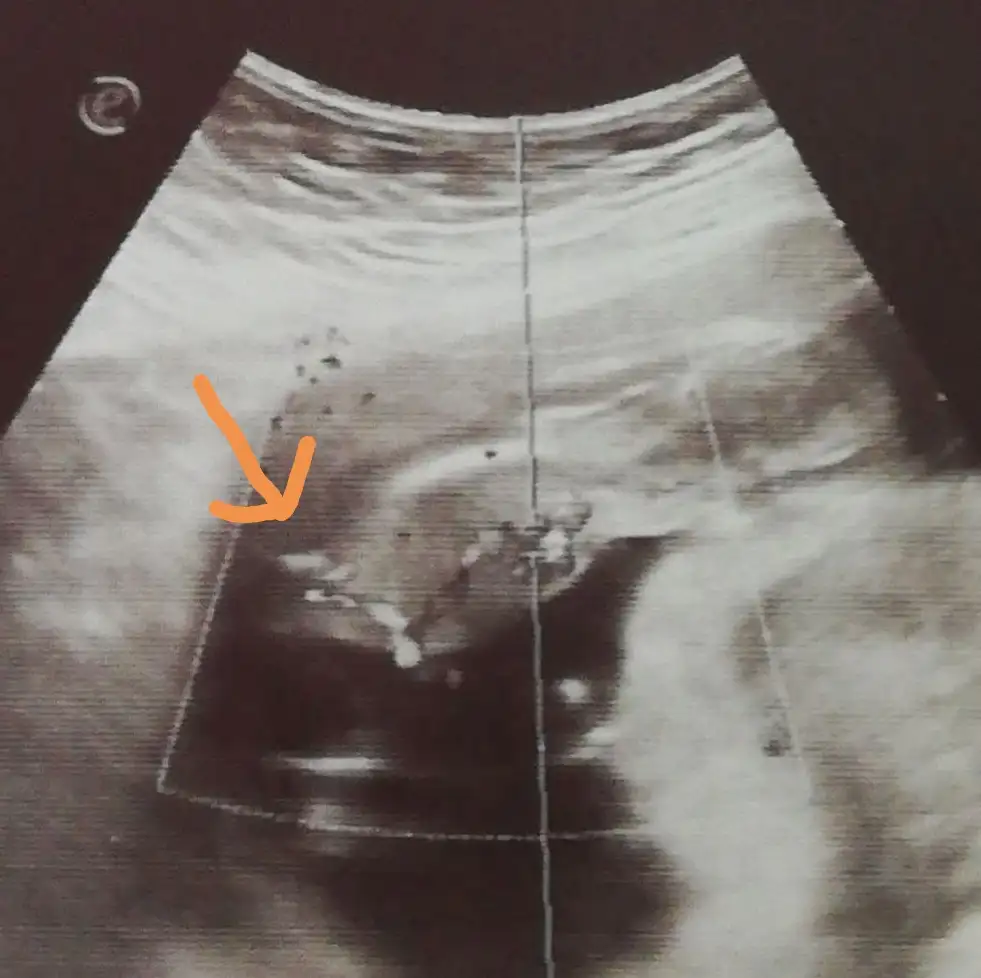

Dün pıhtı gelmişti. Kahverengi lekelenmem devam ediyor. Doktordan geldim. Çok şükür bebeğim iyi. Kanama alanım hala var ama alıştım ben artık, takmıyorum kafaya.